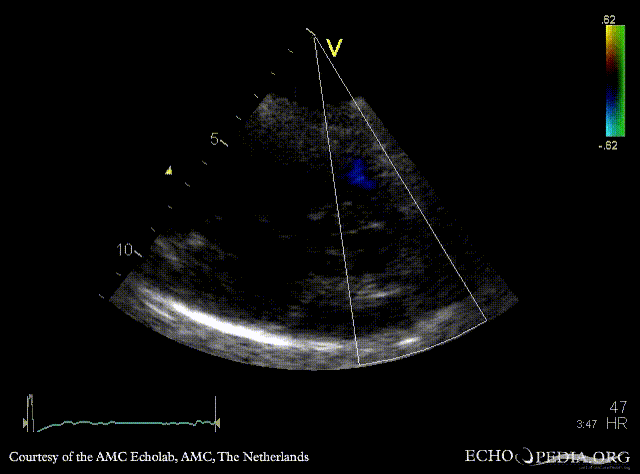

| Continuous-wave signal of flow in arteria pulmonalis | PSAX with Color Doppler |